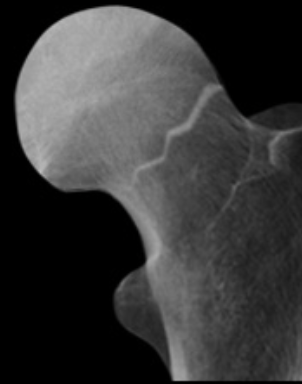

What type of fracture is displayed ? [1]

Explain how you can tell [4]

Intracapsular fracture - Subcapital - AP:

1. Shortened femoral neck

2. Increased density of femoral neck (due to impacted bone)

3. Less troch. is more prominent

4. Shenton’s line is disrupted